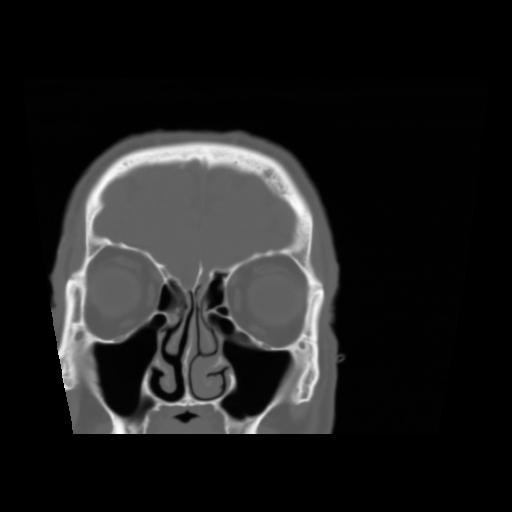

5 CEREBRO,,Coronal,3.000,CEREBRO,Coronal,